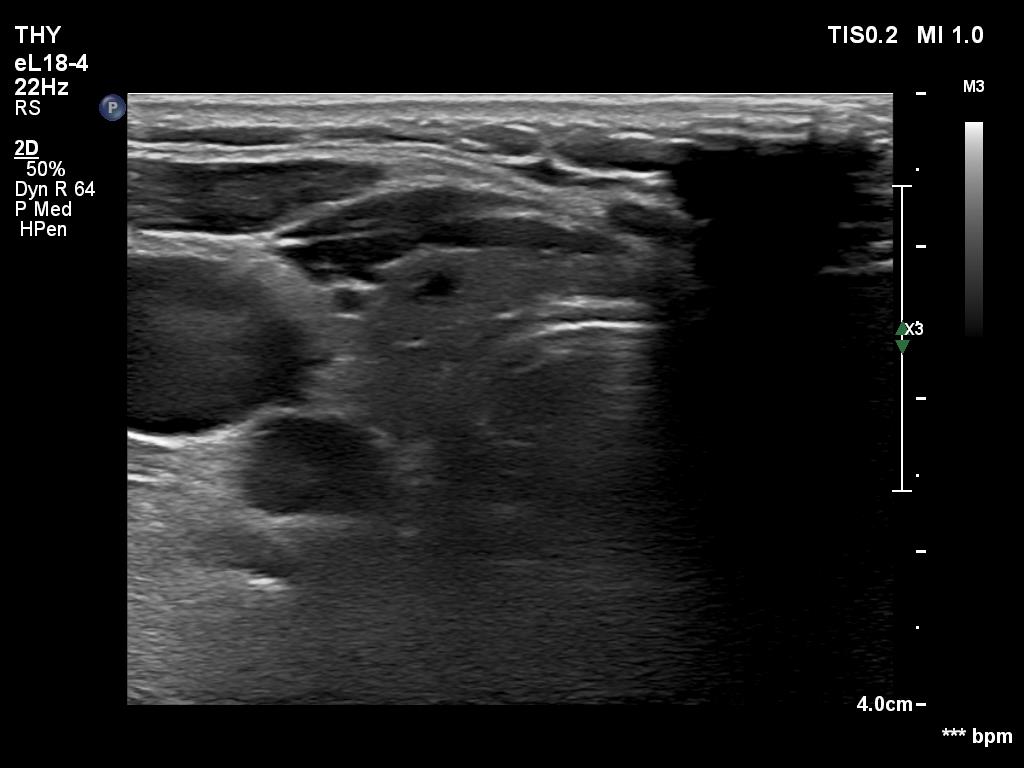

Lymphocytic thyroiditis - case 751

Left lobe

Focal form of lymphocytic thyroiditis is presented. The thyroid has numerous discrete, hypoechoic lesions which correspond to more active foci of thyroiditis. The interpretation of this pattern should not cause concern - these areas are not pathological nodules. The discrete lesions have non-regular, partly clearly lobulated or spiculated margins.